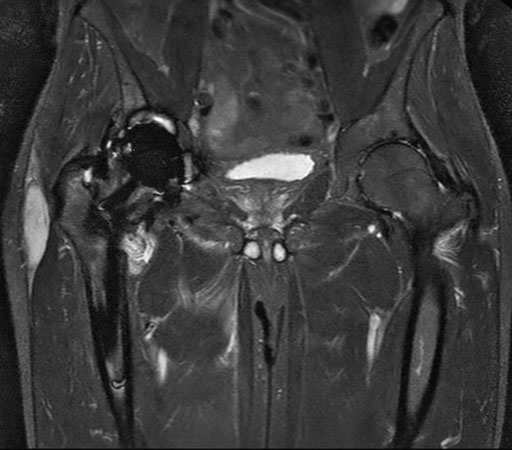

Hip imaging with metal implant using MARS at 1.5T

**Only for use with MR Safe or MR Conditional Implants by strictly following the Instructions for Use.